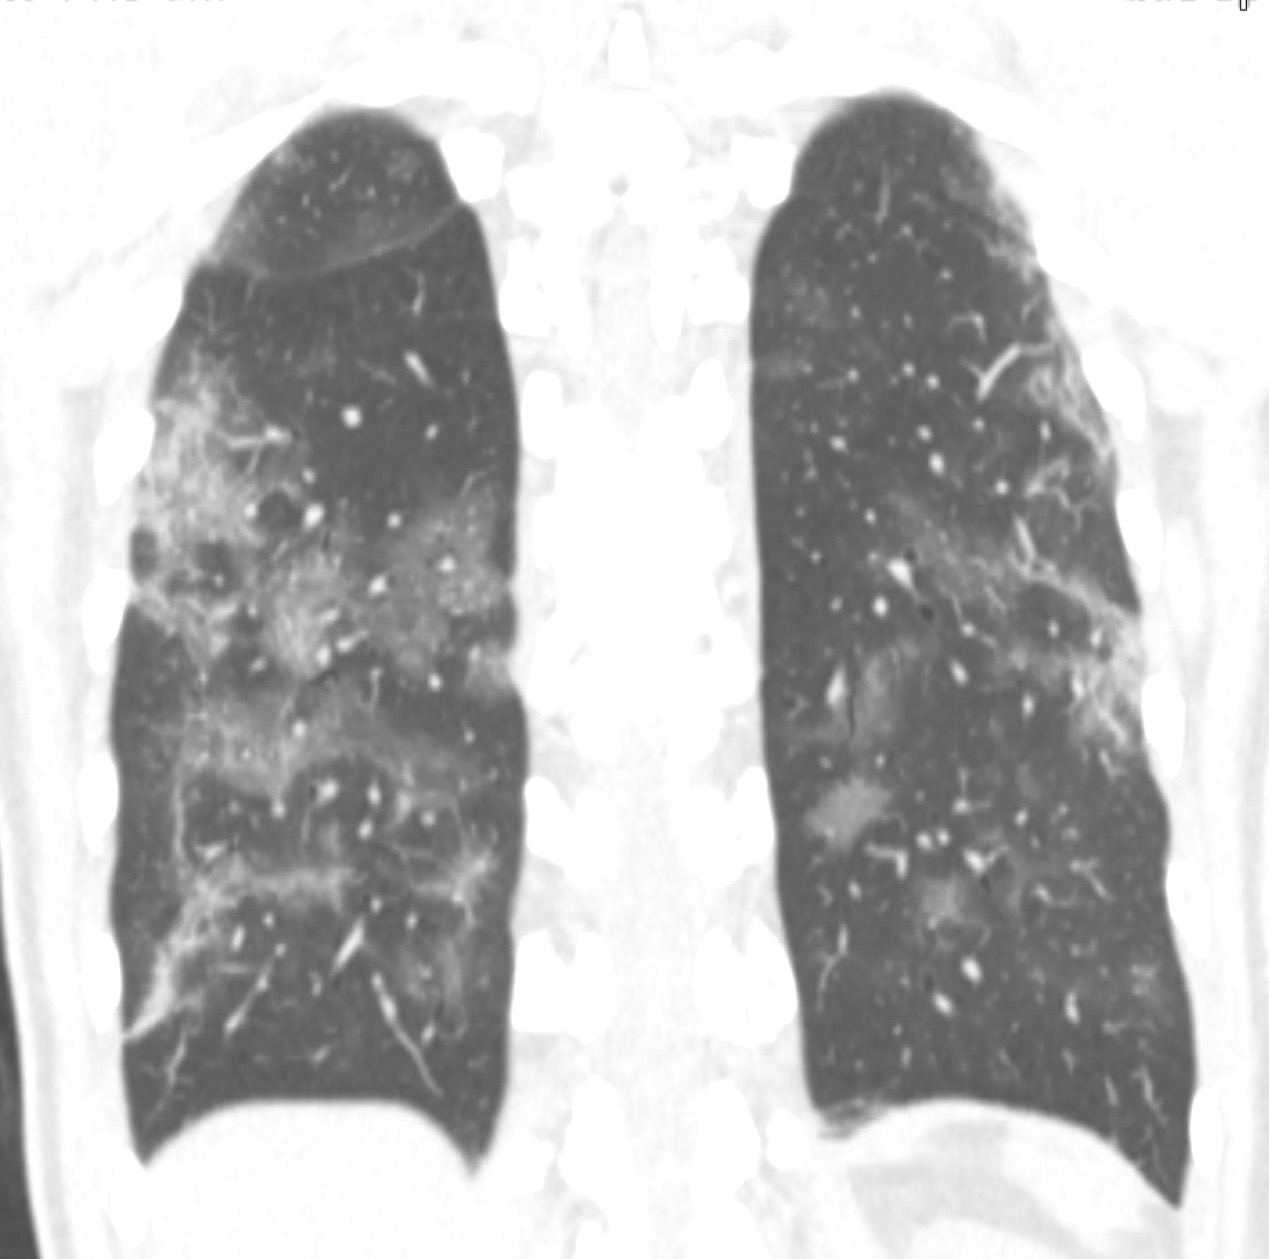

On réalise un scanner thoracique basse dose sans injection iodée. Il montre comme lésion pulmonaire principale des plages de verre dépoli de répartition bilatérale avec une prédominance périphérique et postéro-basale. Il s’y associe quelques plages de condensation de répartition plus anarchique.

Coupe axiale montrant des plages de verre dépoli, de répartition postérobasales bilatérales.

Reconstruction coronale en MinIP (Minimum Intensity Projection, montrant les voxels ayant la valeur la plus basse dans le plan perpendiculaire au plan de coupe) , montrant avec un meilleur contraste les plages de verres de dépoli.